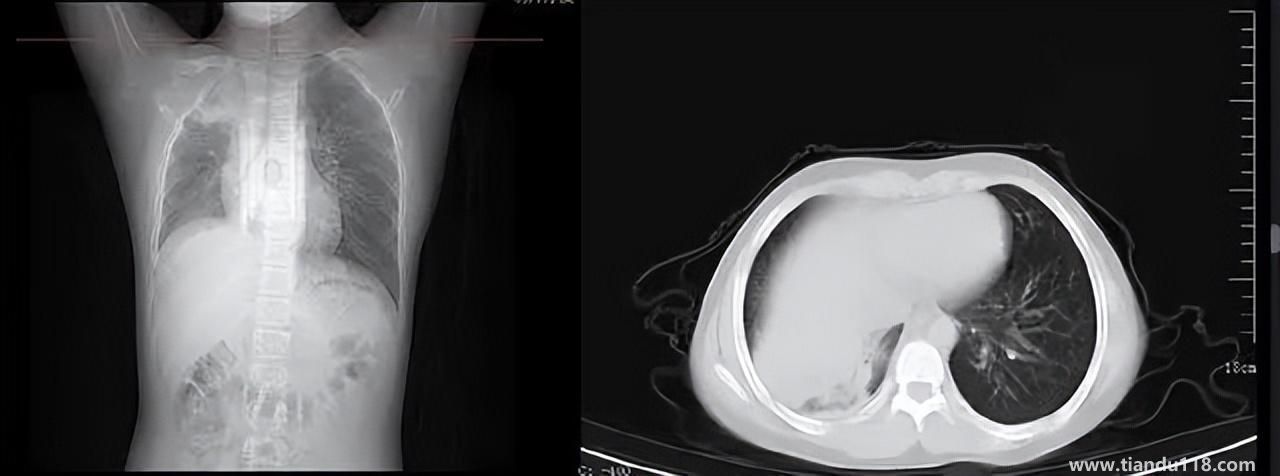

3個(gè)辦法可提前預(yù)警白肺(咋預(yù)防“白肺”) 3個(gè)辦法可提前預(yù)警白肺(咋預(yù)防“白肺”)家里有老人,擔(dān)心出現(xiàn)“大白肺”、“沉默型缺氧”等情況,具體如何應(yīng)對,提前預(yù)警?近日,大象新聞接到諸多咨詢。針對這些問題,大象新聞?dòng)浾咦隽硕喾讲稍L。什么是白肺?對... 小編 2022-12-28 693

男孩咳嗽發(fā)熱在家硬扛成白肺(醫(yī)生表示以下幾種情況別硬“扛”) 男孩咳嗽發(fā)熱在家硬扛成白肺(醫(yī)生表示以下幾種情況別硬“扛”) 近日,一名12歲男孩咳嗽一周不就醫(yī),一側(cè)肺部“扛”成了“白肺”?!氨е鴥e幸心理一直在家硬‘扛’,沒想到‘扛’出這么重的?。 焙⒆蛹议L悔不... 小編 2022-12-28 939

為何有人出現(xiàn)“白肺”?專家回應(yīng)和疫苗接種無關(guān) 為何有人出現(xiàn)“白肺”?專家回應(yīng)和疫苗接種無關(guān)國務(wù)院聯(lián)防聯(lián)控機(jī)制12月27日召開新聞發(fā)布會(huì),針對有媒體提問稱,從近期公眾的反映情況看,有的新冠病毒感染者在就診過程中發(fā)現(xiàn)了肺炎或者是CT出現(xiàn)了“白肺”的現(xiàn)... 小編 2022-12-27 817

感染新冠會(huì)變白肺?醫(yī)生:有年輕病例 感染新冠會(huì)變白肺?醫(yī)生:有年輕病例感染新冠會(huì)變白肺嗎?對此,有專家表示,造成“白肺”情況有很多種,感染新冠只是一種可能。少量患者肺有滲液 ,咳嗽不會(huì)引發(fā)白肺,有年輕人病例。... 小編 2022-12-27 608